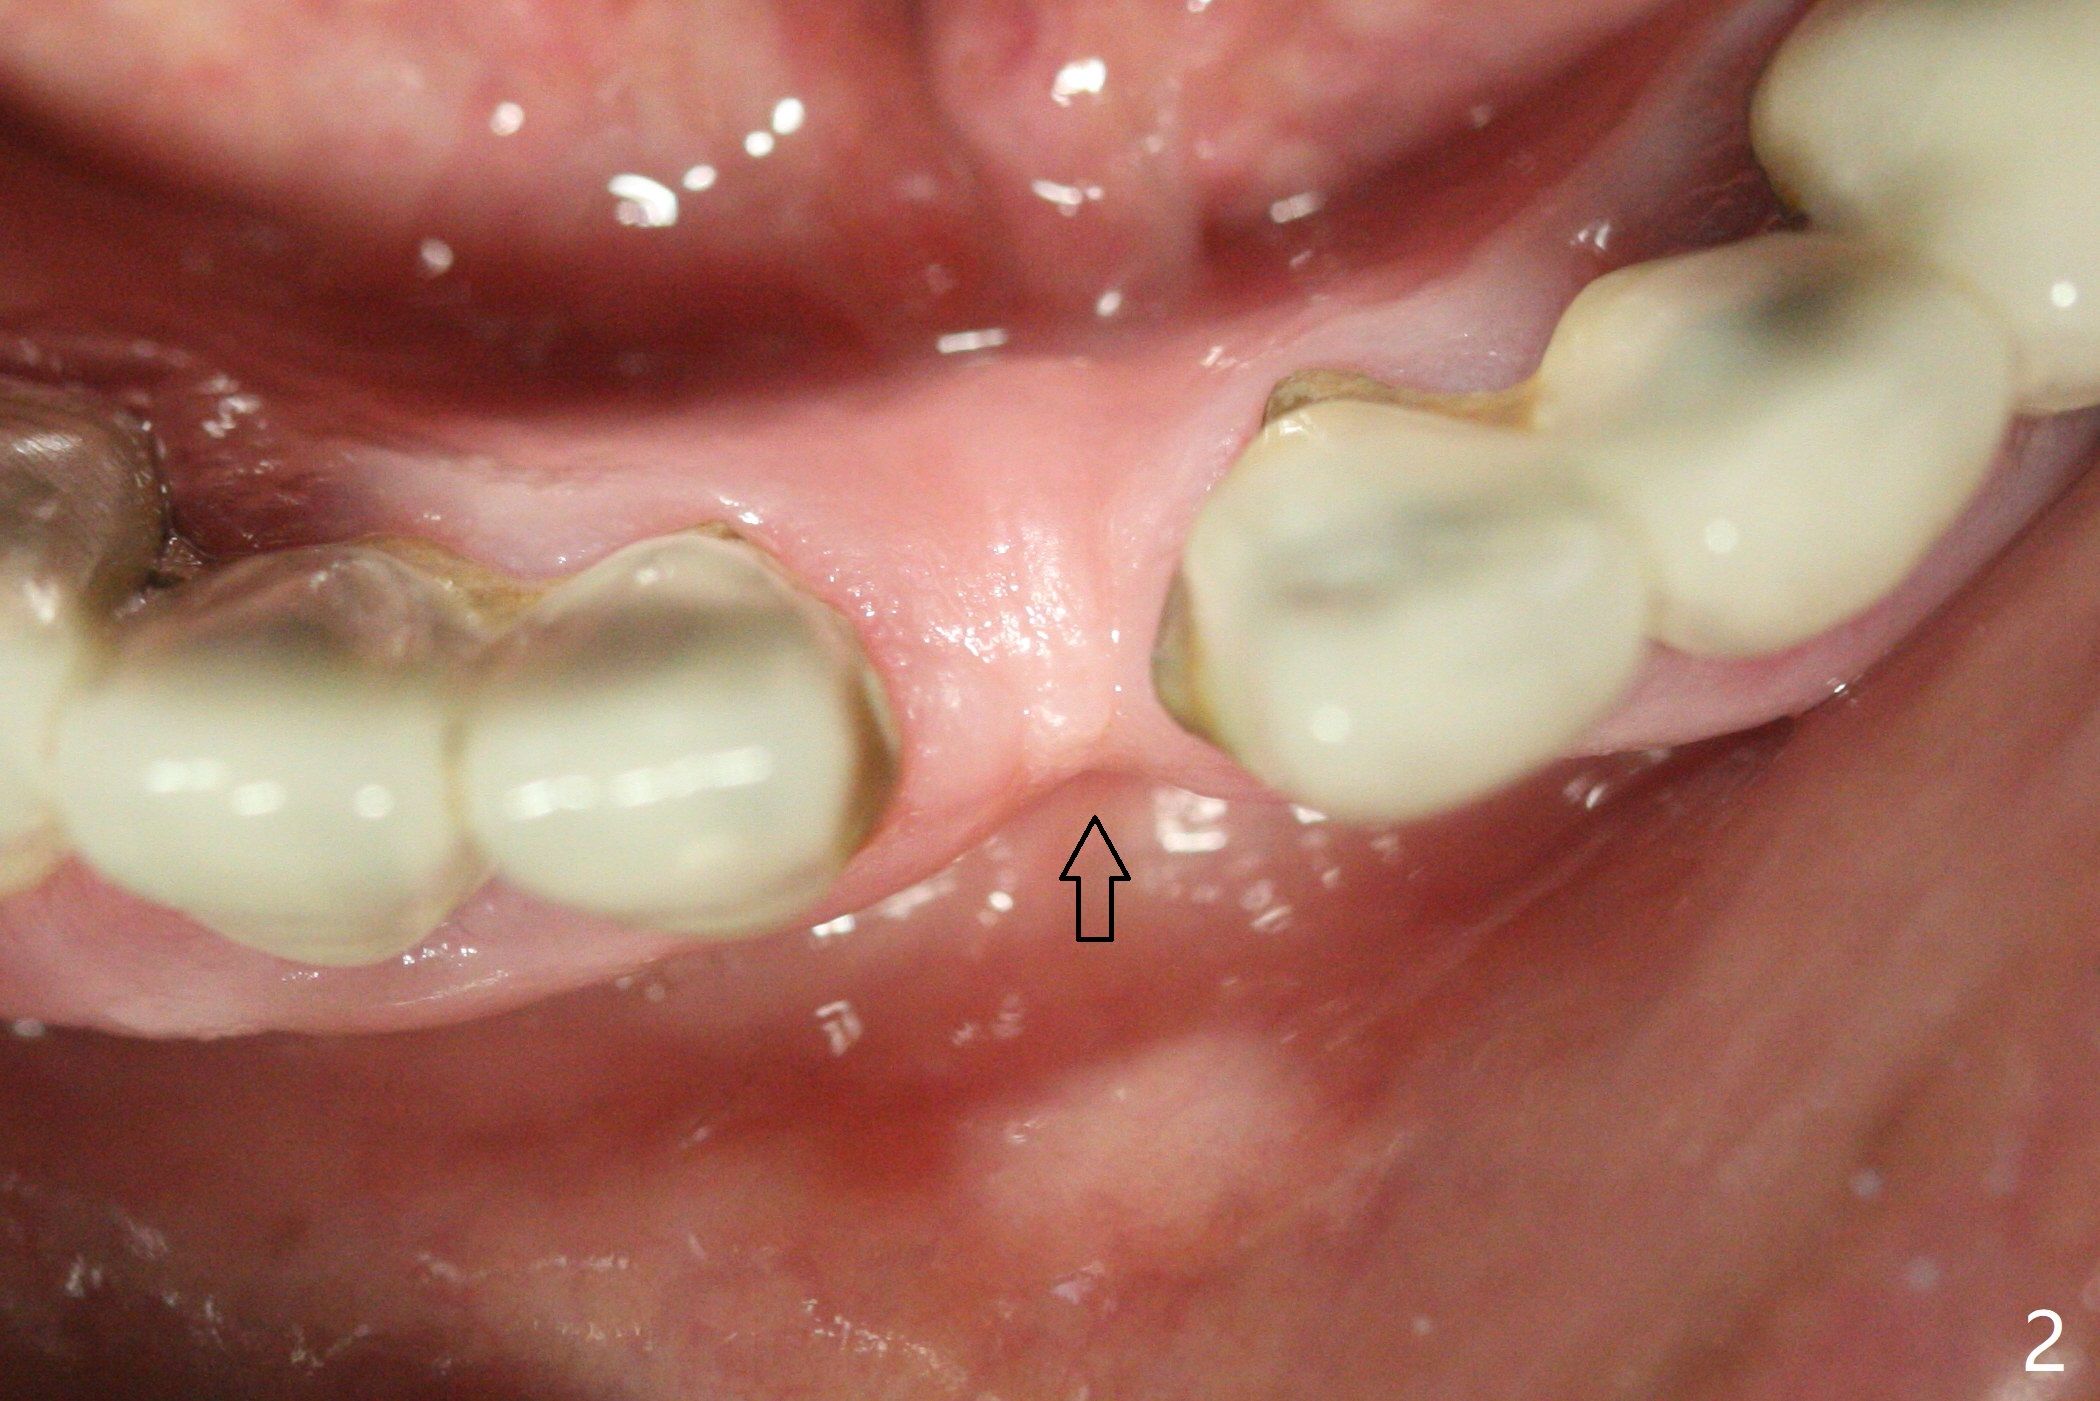

种植前与66岁女病人再次讨论下前牙正中种植可能产生不对称问题,她好像不在乎。术前检查显示下前牙正中间隙偏左(图一),处理似乎容易,但是牙槽嵴相当狭窄(图一 *,二 箭头)。牙槽嵴切除后(大约3 毫米宽(颊舌侧)),初期钻洞似乎偏移右边(图三),矫正后(图四),植入2乘10(4)毫米连体植体(图五,比预计小,因为骨质薄),放置骨粉(图五,六 *)和膜,缝合,制作即刻修复物(图七 T),病人满意,牙槽骨饱满了。术后一个多月临时牙冠取出修正,伤口愈合,由于植骨颊侧没有凹陷(图八),而舌侧隆起(图九:*,与图二术前对比)。其实病人不小心吃牛肉时损伤植体,疼痛几天。尽管最近吃饭时植牙又受伤,但是没有松动,也没有骨质吸收,就是局部结石多(图十,术后四个月)。正式牙冠术后4.5个月粘固(图十一)。